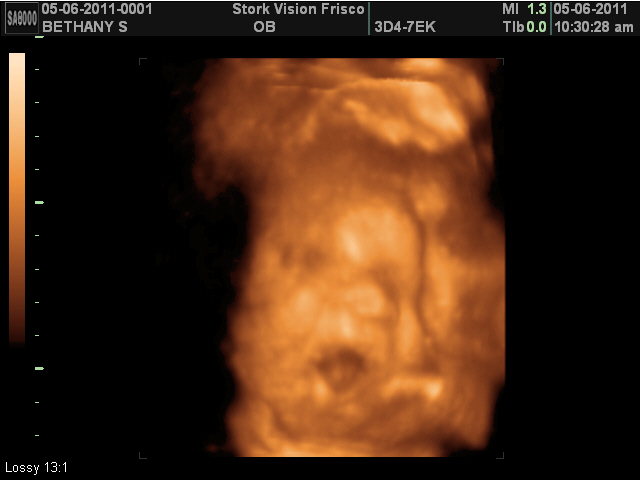

The tech commented on her cheeks almost right away. I said she comes by them honestly. :)

Like with every other ultrasound we've had, her hand was up by her face. She would not move it for anything! She wasn't sucking on her thumb or fingers. She just liked to have her face covered. I said that she was going to be "shy" like Michael. He said he was just thinking the same thing.

Her foot is up near her face too. She is literally folded in half.

This picture cracks me up! On the video you can see that she is yawning, but in this photo it looks to me like she is in shock or saying something like "Oh my!".

Such a scowl! It's amazing to me the facial expressions they can have at this point.

Michael is convinced she has my nose.

We got a smile! It may be my smile! Sometimes when I smile, for whatever reason, the edges of my mouth turn down. I never really noticed it until I married Michael. He pointed it out. He thinks it's funny. He calls it my "frown smile". He's also the one that noticed in this picture that Olivia has a frown smile. Crack me up!

We still think she has Michael's chin.